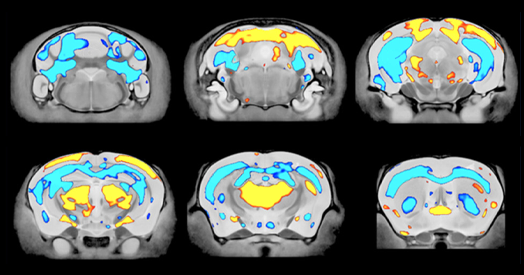

Un estudio en Nature revisó la poca investigación sobre autismo en adultos mayores, conectándolo con problemas de salud comunes en la vejez como Parkinson y demencia. También se miraron la memoria, la menopausia y marcadores en sangre. Otra investigación reciente analizó cómo cambia el cerebro de ratones con autismo.

La investigación sobre el autismo en adultos mayores es un área significativamente subestudiada, lo que plantea preocupaciones sobre la falta de comprensión de cómo esta condición se desarrolla y afecta a las personas a medida que envejecen. Estudios recientes han comenzado a explorar las conexiones entre el autismo y diagnósticos relacionados con la edad, como la enfermedad cardíaca, la demencia y la enfermedad de Parkinson, lo que sugiere una posible relación entre el autismo y un mayor riesgo de desarrollar estas condiciones. Además, investigaciones más recientes se han centrado en la memoria a corto y largo plazo, los aspectos físicos y psicológicos de la menopausia, y los marcadores sanguíneos, lo que podría proporcionar una comprensión más profunda de cómo el autismo afecta a las personas a medida que envejecen.

La relevancia de este tema radica en su impacto en la calidad de vida de las personas con autismo que envejecen, ya que pueden enfrentar desafíos sociales, como la pobreza y la falta de vivienda, así como cambios en la estructura cerebral que pueden afectar su salud y bienestar. Es fundamental abordar esta brecha en la investigación para desarrollar estrategias efectivas de apoyo y atención para las personas con